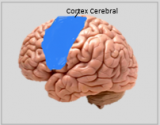

A neuroanatomia é o ramo da anatomia que estuda a anatomia do sistema nervoso, ou seja, a estrutura, a função e a organização do sistema nervoso. O sistema nervoso é um dos sistemas mais complexos do corpo humano e inclui o cérebro, a espinal medula, os nervos periféricos e os gânglios nervosos. A neuroanatomia preocupa-se com a forma como estas estruturas estão ligadas entre si, como os sinais são transmitidos entre as células nervosas e como as diferentes partes do sistema nervoso trabalham em conjunto para controlar as funções corporais e cognitivas. Os neuroanatomistas utilizam técnicas de imagiologia avançadas, como a ressonância magnética (MRI), a tomografia por emissão de positrões (PET) e a microscopia para visualizar as estruturas e funções do sistema nervoso.